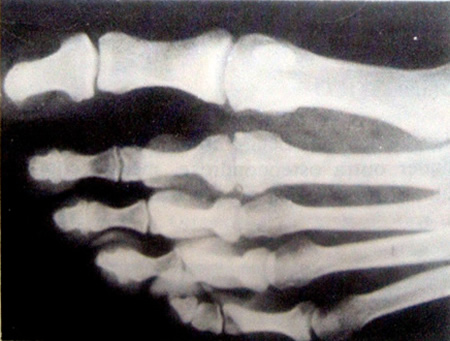

O paciente queixa-se de dor no antepé quando fica em pé e caminha. O exame revela aumento de volume e dor á pressão local assim como restrição antálgica do movimento na articulação metatarsofalângica. O aspecto radiológico é típico de todas as osteocondroses (Fig. 13-19).

Figura 13-19. Osteocondrose da cabeça do segundo osso do metatarso (doença de Freiheug) em tinha moça de 19 anos. A cabeça normalmente com forma de cúpula tornou-se achatada, longa e irregular, resultando em incongruência articular com doença articular degenerativa precoce. Originalmente. este metatarsal teria sido mais longo que o primeiro; a hipertrofia da diáfise sugere que ele esteve suportando carga excessiva por muitos anos.